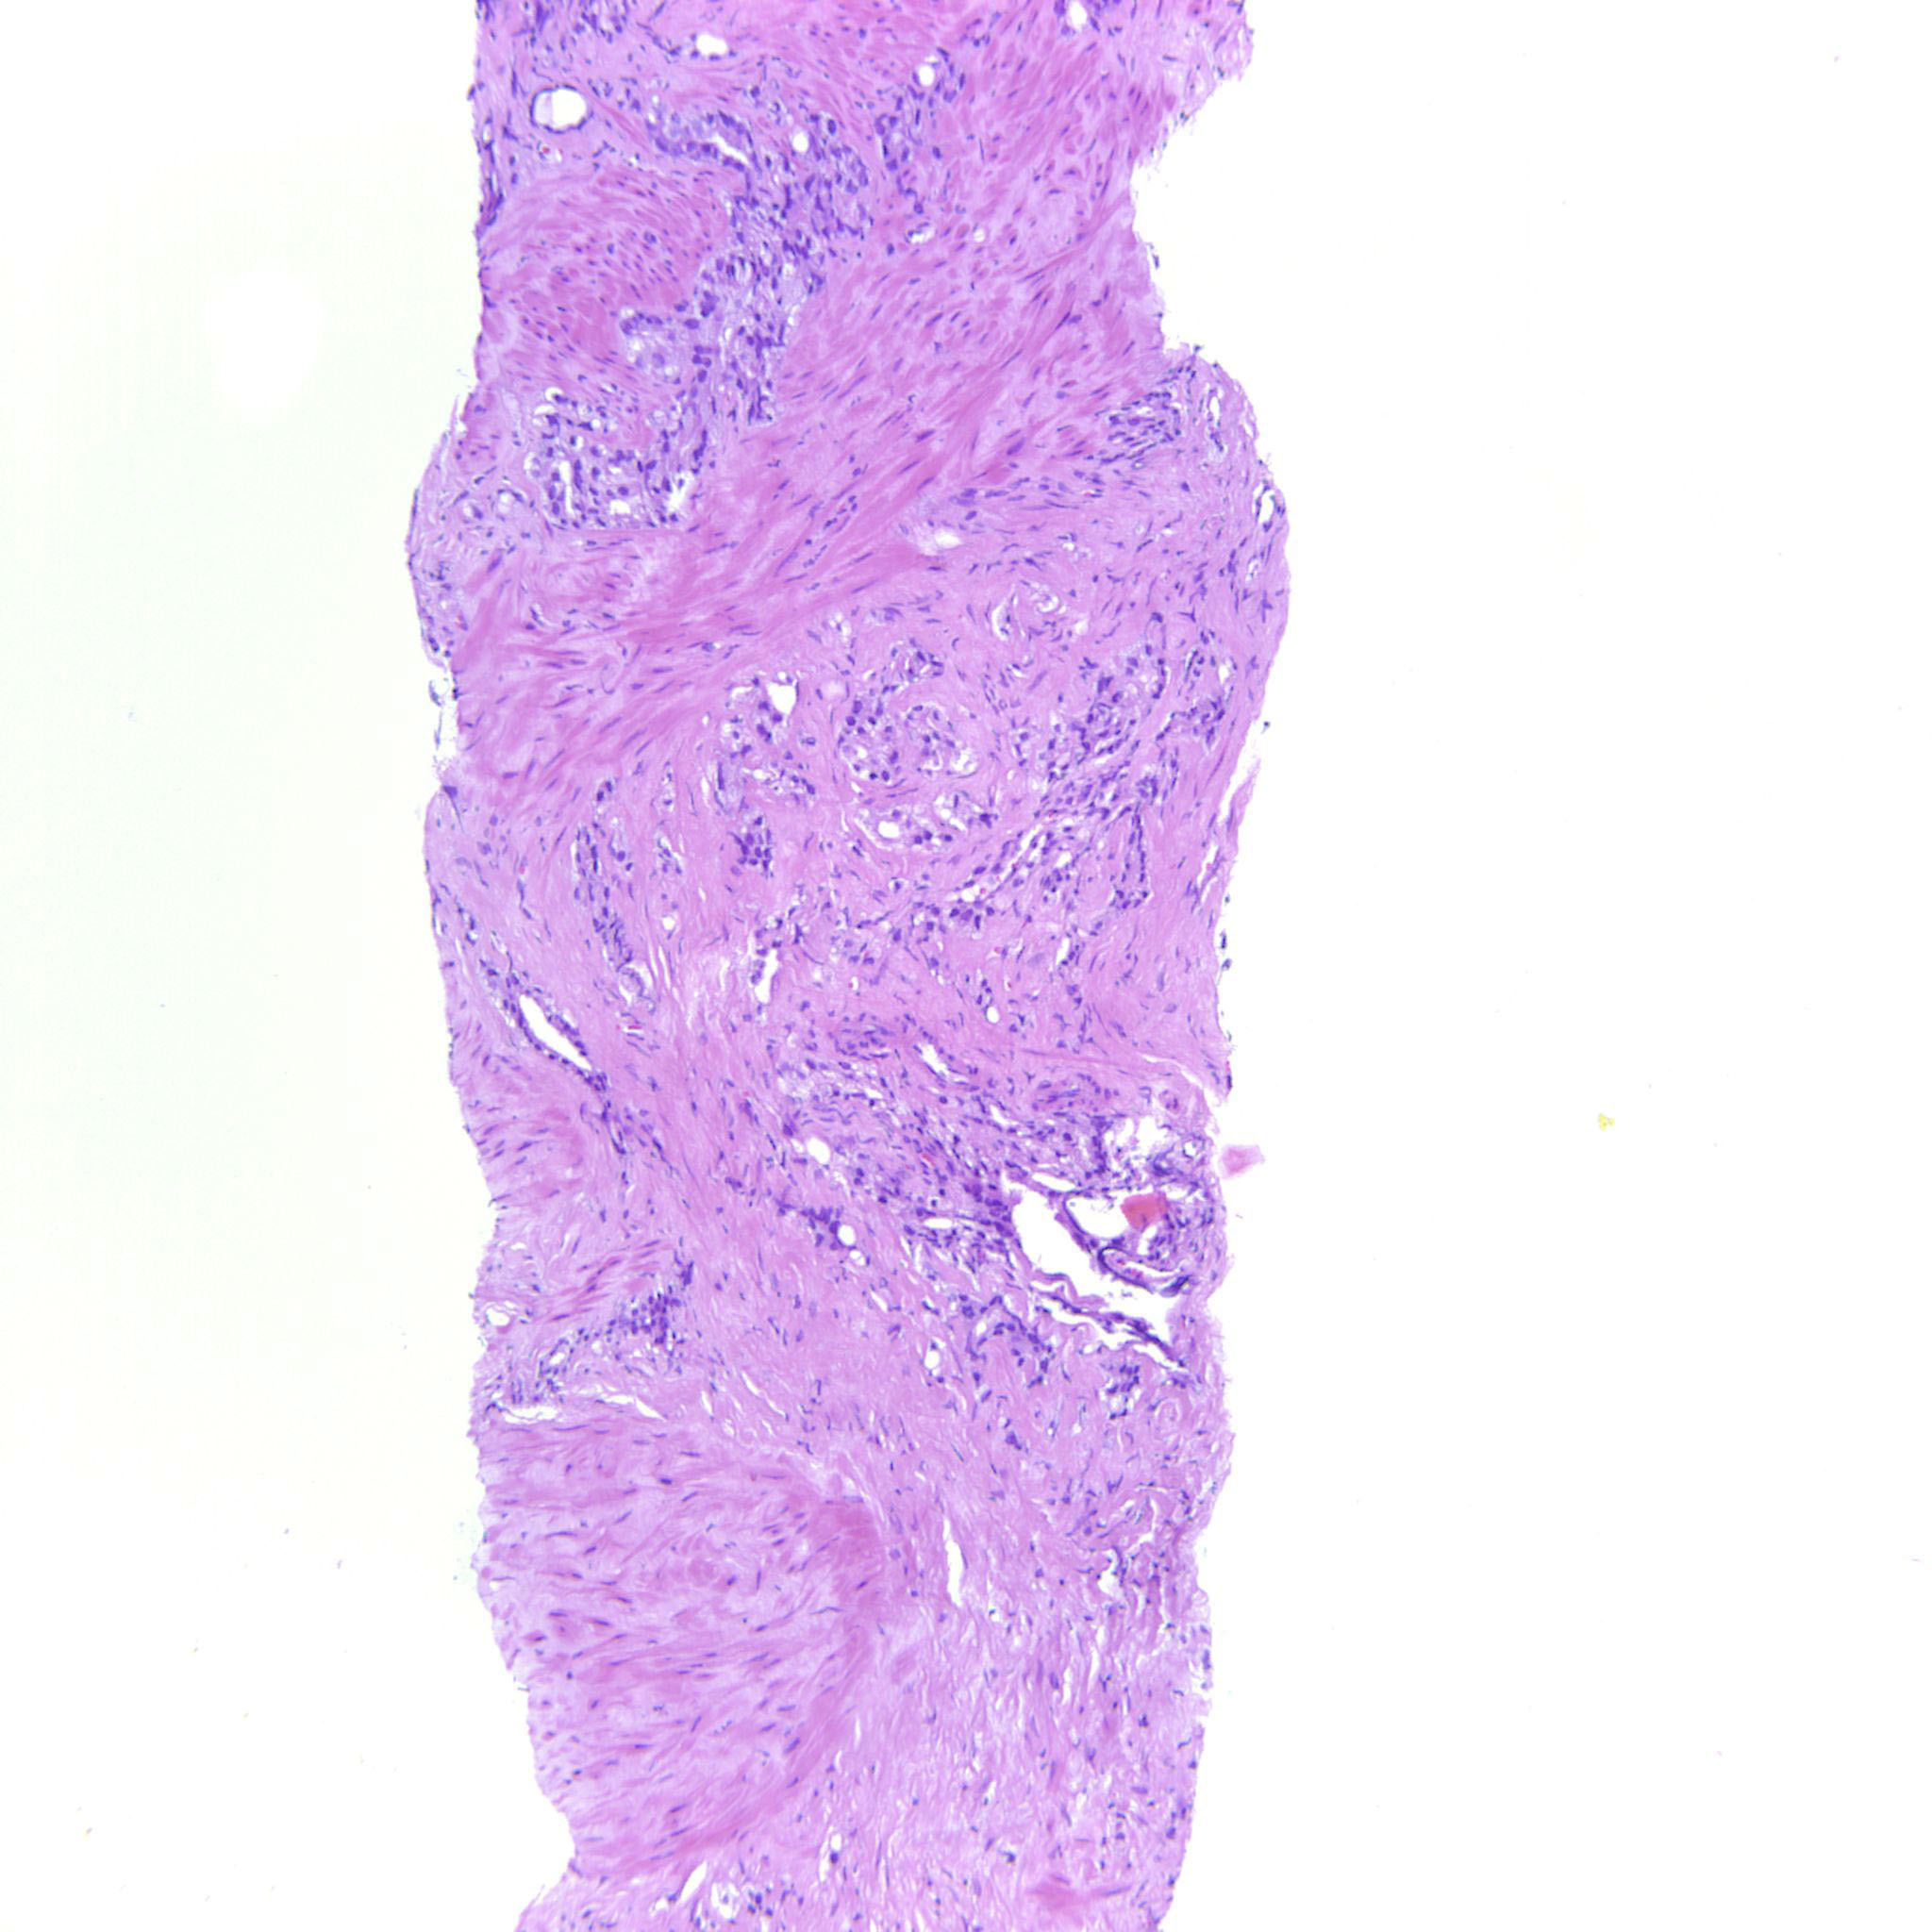

Prostate cancer grading

Case ID: 635